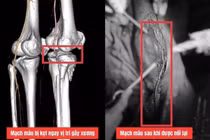

Trong ca mổ cấp cứu lần đầu, ê-kíp tua trực cấp cứu đã phát hiện vỡ tá tràng, vỡ gan trung tâm, tổn thương đầu tụy, chảy máu ổ bụng cùng nhiều cơ quan khác bị dập nát. Đây là những tổn thương được coi là “ác mộng” trong phẫu thuật bụng, bởi tá tràng là nơi lưu thông hàng lít dịch tiêu hóa, mật và tụy mỗi ngày.

Trong bệnh cảnh đa chấn thương nặng, các bác sĩ đã khâu cầm máu gan, xử lý vỡ tá tràng, nối vị – tràng, đóng môn vị, dẫn lưu ổ bụng và cố định xương hai chân. Hậu phẫu, bệnh nhân được chuyển sang hồi sức tích cực – mở đầu cho một hành trình đầy thử thách.